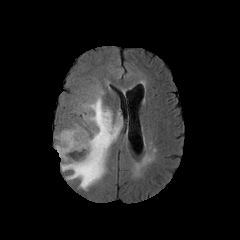

We introduce a neural network framework, utilizing adversarial learning to partition an image into two cuts, with one cut falling into a reference distribution provided by the user. This concept tackles the task of unsupervised anomaly segmentation, which has attracted increasing attention in recent years due to their broad applications in tasks with unlabelled data. This Adversarial-based Selective Cutting network (ASC-Net) bridges the two domains of cluster-based deep learning methods and adversarial-based anomaly/novelty detection algorithms. We evaluate this unsupervised learning model on BraTS brain tumor segmentation, LiTS liver lesion segmentation, and MS-SEG2015 segmentation tasks. Compared to existing methods like the AnoGAN family, our model demonstrates tremendous performance gains in unsupervised anomaly segmentation tasks. Although there is still room to further improve performance compared to supervised learning algorithms, the promising experimental results shed light on building an unsupervised learning algorithm using user-defined knowledge.